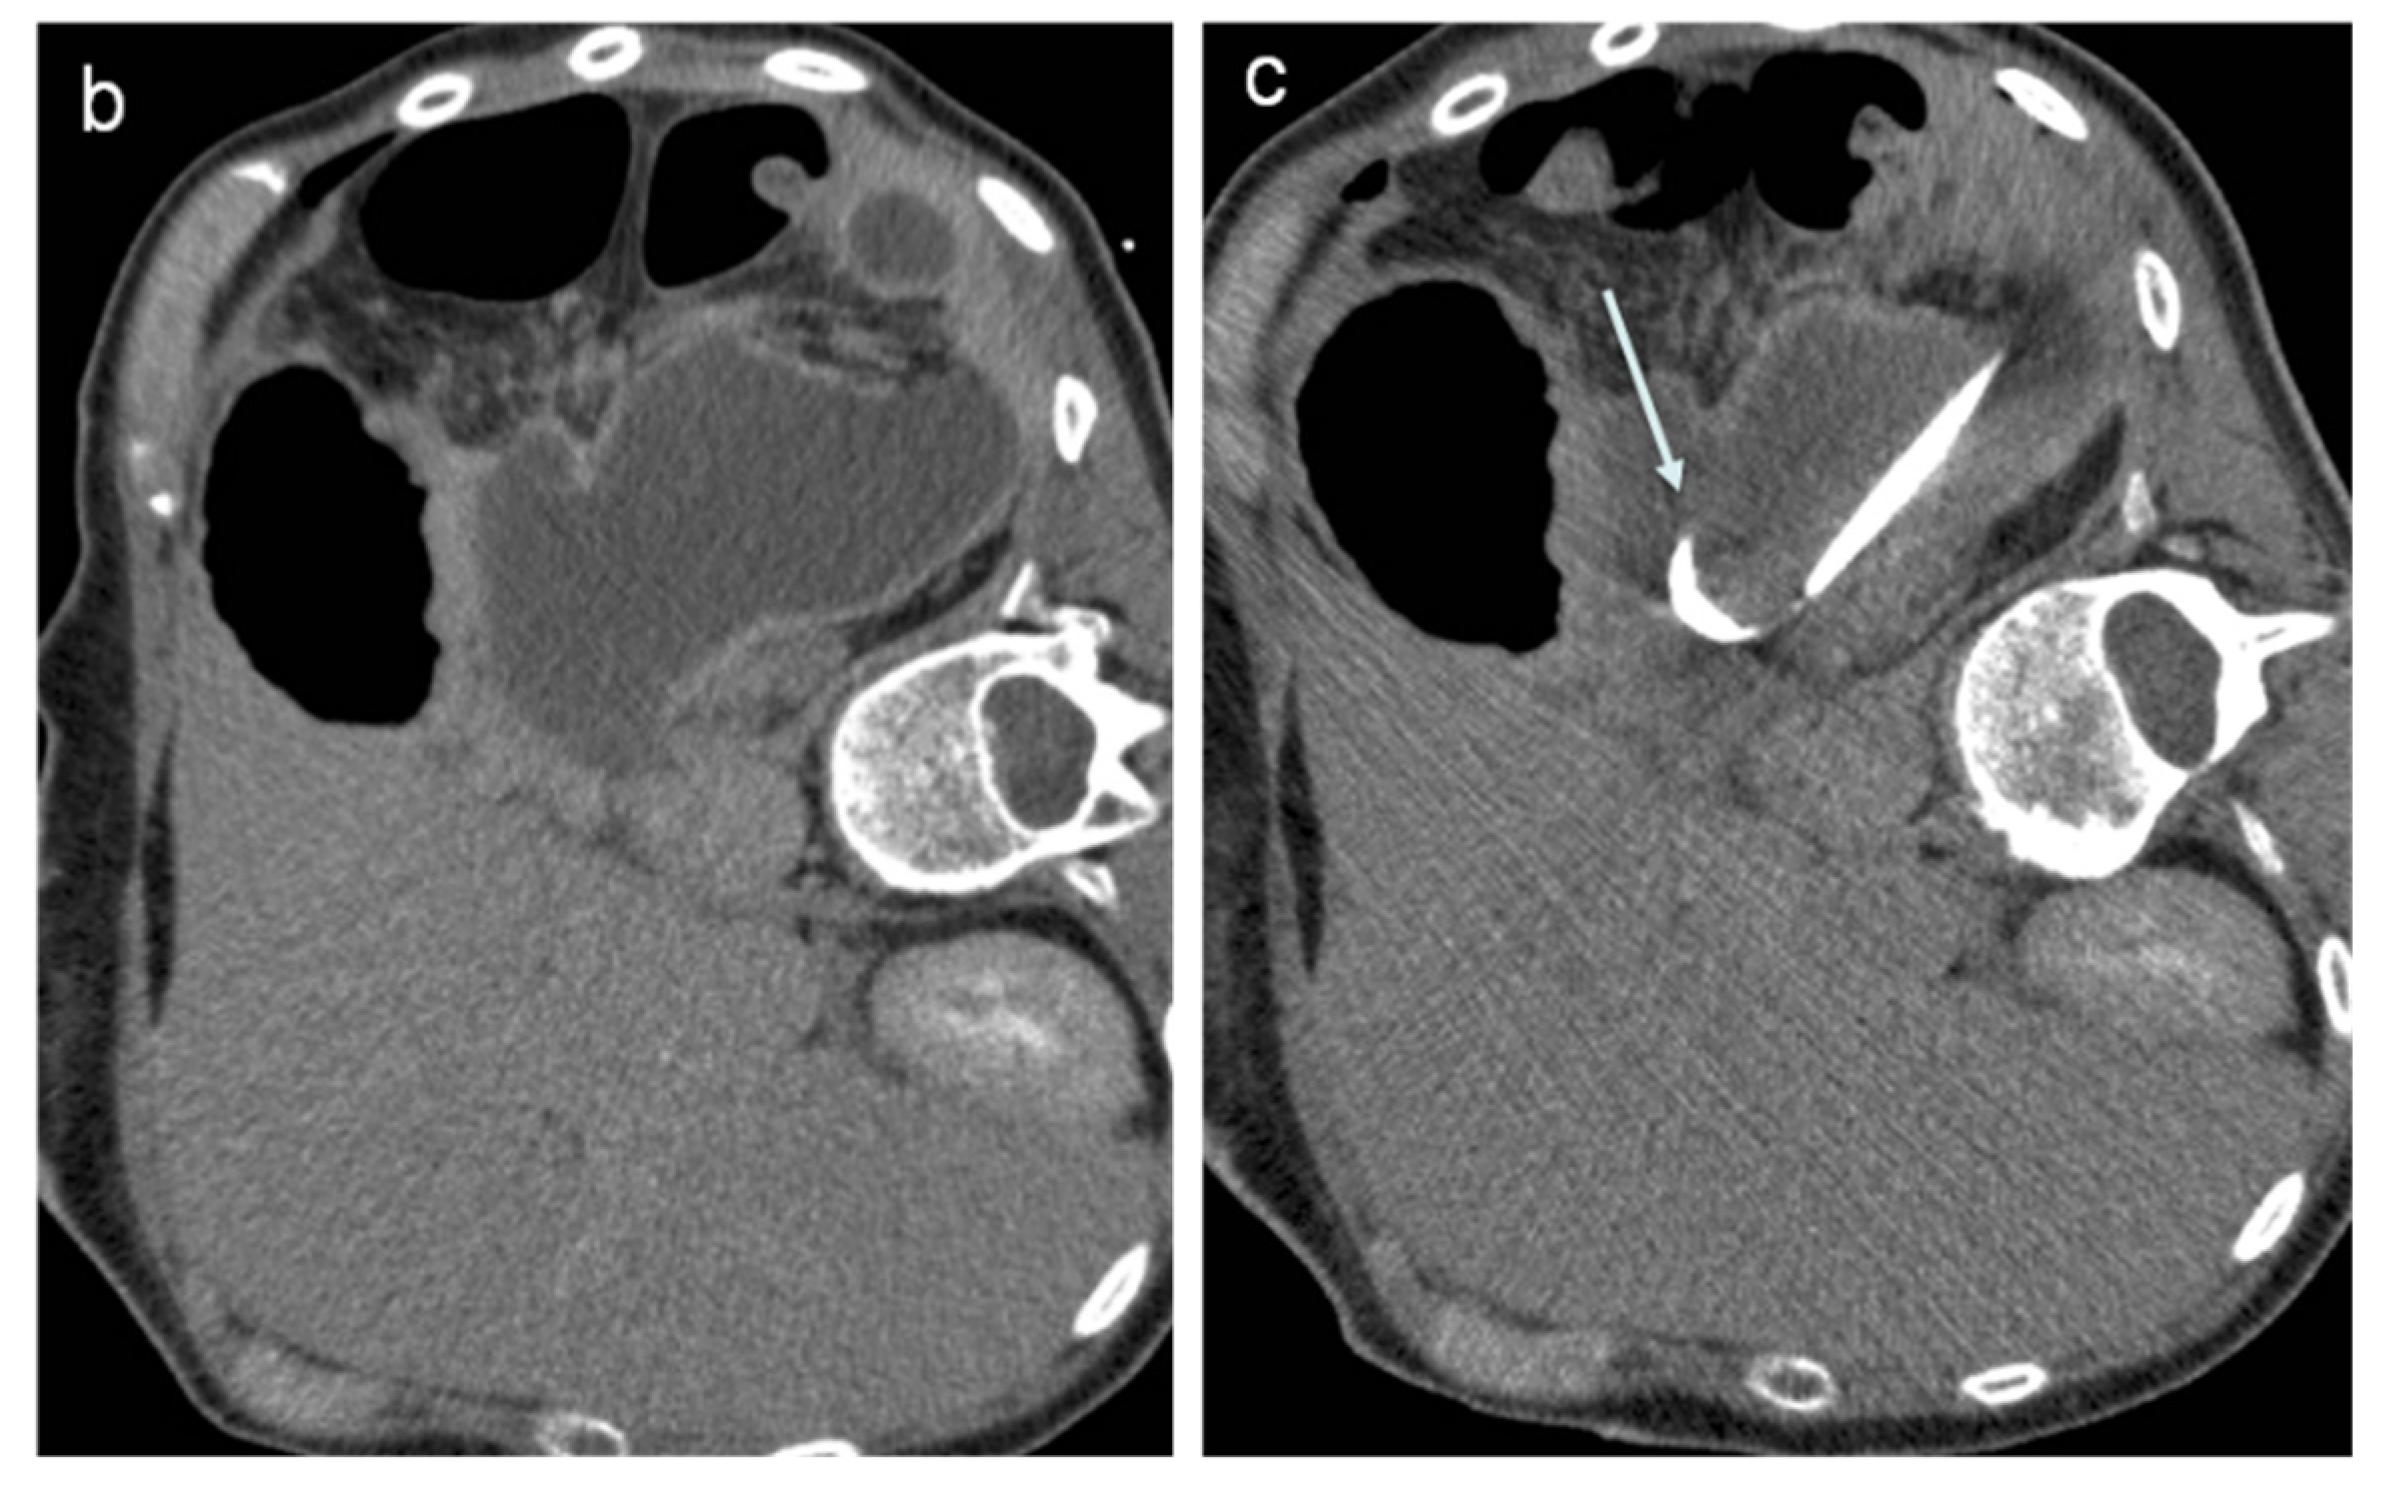

2. Percutaneous Fluid Collection Drainage